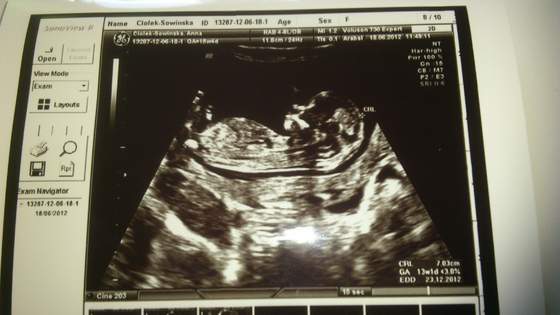

Sowinka, nie moglo byc inaczej niz wszystko w porzadeczku

oo 7 cm fasoliny

jaki ma fajny brzuszek

no jeszcze chwileczke i pokazesz nam swojego pasazera, jej jak to zlecialo